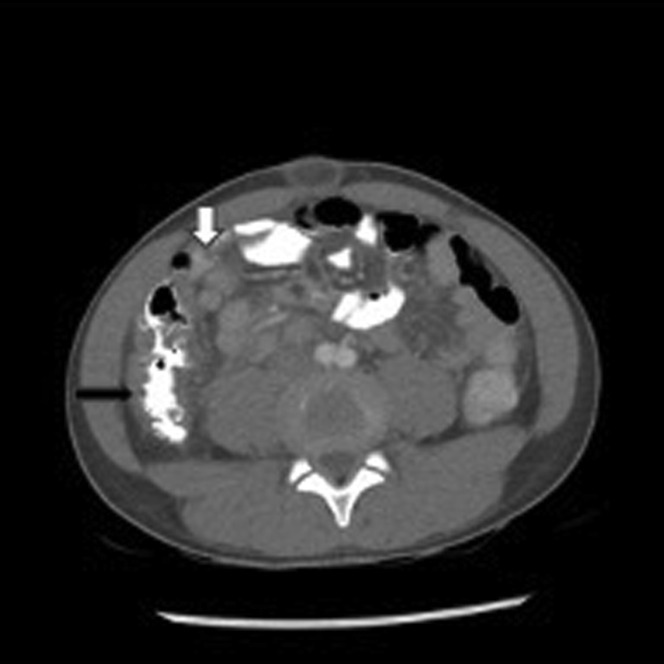

Abdominal pain and vomiting can occur in 60% of patients with MIS-C and can be of such severity as to be mistaken for acute appendicitis.60 The possibility of MIS-C coexisting with acute appendicitis should be considered.69 , 70 Patients with severe acute COVID-19 can present with gastrointestinal symptoms but these are usually not as severe as those seen in patients with MIS-C. Feldstein and colleagues61 reported gastrointestinal symptoms on presentation in 90% of patients with MIS-C compared with 58% of patients with severe acute COVID-19. Abdominal imaging in patients with MIS-C have demonstrated inflammation, including mesenteric adenopathy, mesenteric edema, ascites, bowel wall thickening, and gallbladder wall thickening (Fig. 4 ).

Fig. 4.

Abdominal CT of 11-year-old African-American male with MIS-C who presented with fever, mucocutaneous symptoms, severe abdominal pain, vomiting, and CoV-2 antibody (Ab) IgG+. Bowel wall thickening of ascending colon (black arrow) with several enlarged lymph nodes (white arrow).